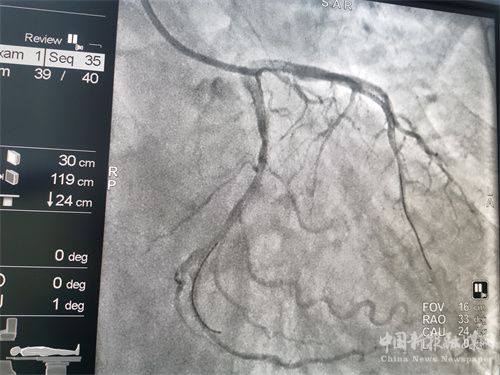

患者溶栓成功后,經(jīng)患者及家屬同意后行冠狀動(dòng)脈造影檢查,患者冠脈顯示前降支次全閉、回旋支狹窄95%、右冠近端狹窄85%,病情緊急,李維軍、楊亮主任向家屬詳細(xì)講明病情后,予以開(kāi)通前降支和回旋支,植入支架3枚。手術(shù)全程用時(shí)不到一個(gè)小時(shí)。目前,患者病情穩(wěn)定。